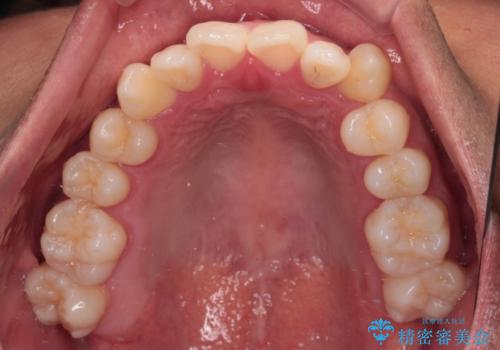

- 上下前歯部のデコボコを主訴として来院された患者様です。

上顎の歯列弓が下顎に対して狭いため、臼歯のかみ合わせがが咬頭対咬頭の状態です。

上顎の急速拡大装置を使用して、上顎骨を側方に拡大することで上顎歯列弓を拡大し、それに伴い下顎歯列弓も拡大できるようにして、歯列を整えていくこととしました。

歯列弓の拡大により約1年で矯正治療を終えることができました。

正中も合わせることができ、非常にきれいに仕上がりました。